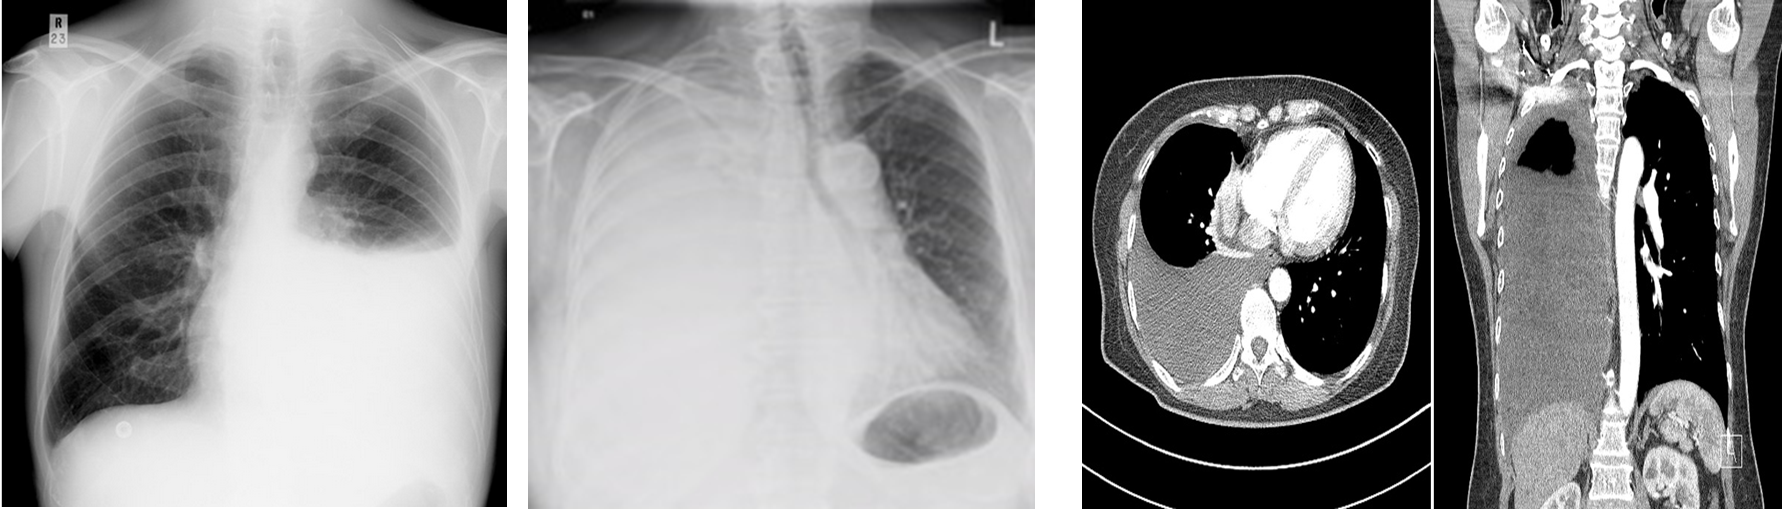

Hemothorax

_____ is a collection of the blood within the plural space (between visceral and parietal layers).

This pathology typically has an attenuation of 35-70 HU.

Pleural effusion typically has an attenuation of 5-14 HU.